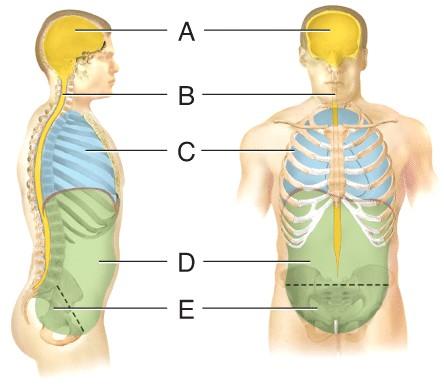

Name the cavity A.

dorsal

cranial

vertebral

ventral

cranial

Name the cavity C.

cranial

thoracic

abdominal

pelvic

thoracic

Name the cavity formed by A and B.

abdominopelvic

ventral

dorsal

pelvic

dorsal

Name the cavity formed by D and E.

ventral

abdominopelvic

dorsal

thoracic

abdominopelvic

Name the cavity formed by C, D and E.

dorsal

cranial

ventral

abdominopelvic

ventral

Name the cavity E.

cranial

pelvic

abdominal

thoracic

pelvic